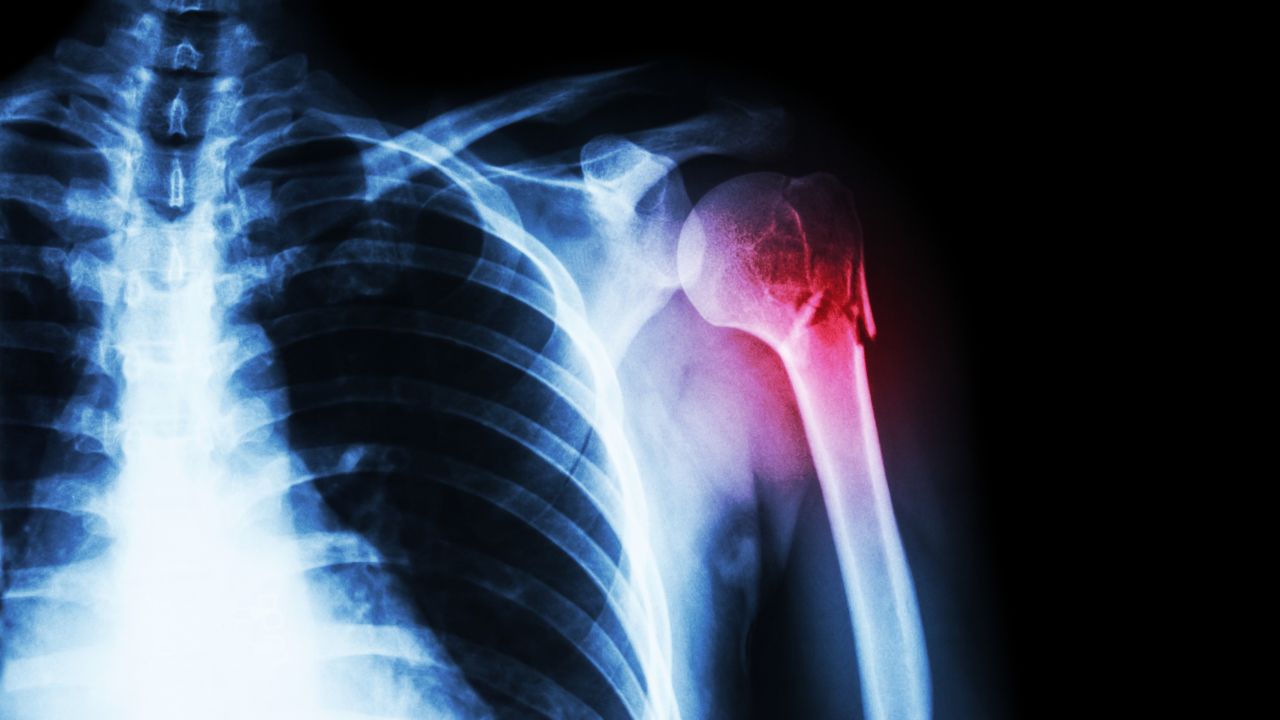

رادیوگرافی (اشعه ایکس)

رایج‌ترین روش برای بررسی انواع شکستگی‌ها، تصاویر رادیوگرافی است. این نوع تصویربرداری می‌تواند وجود ترک یا شکست در استخوان را مشخص کند و شدت آسیب را نشان دهد.